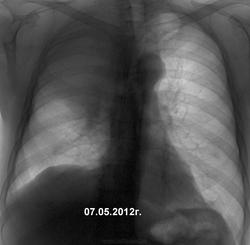

Первый, который с таким "эхинококком" в верхней доле справа, из-за которого исчезли передние отрезки рёбер и возник паралич правого диафрагмального нерва, явно опоздал к онкологу.

с первым соглашусь имеет место объемный процесс, средостение смещено в противоположную сторону, атрофия передних отрезков ребер, правый корень явно расширен за счет л/у.

Повторюсь, архива нет (не спорю, было бы интересней и легче). Первый бомжеватого вида, жалобы на кашель. Написал предположительно центральный рак в/дол. бронха с ателектазом доли, направил на КТ, консультацию онколога. Думаю не только на лечение, но и на КТ бабла не соберет. Второй - то ли дядя, то ли знакомый коллеги, живет в селе, то же без архива. Стажа в шахте не уточнил, но, хоть и видя очаговые изменения в легких, предположил опухоль в В3, направил на КТ. Тут пообещали результаты принести. Выложу.